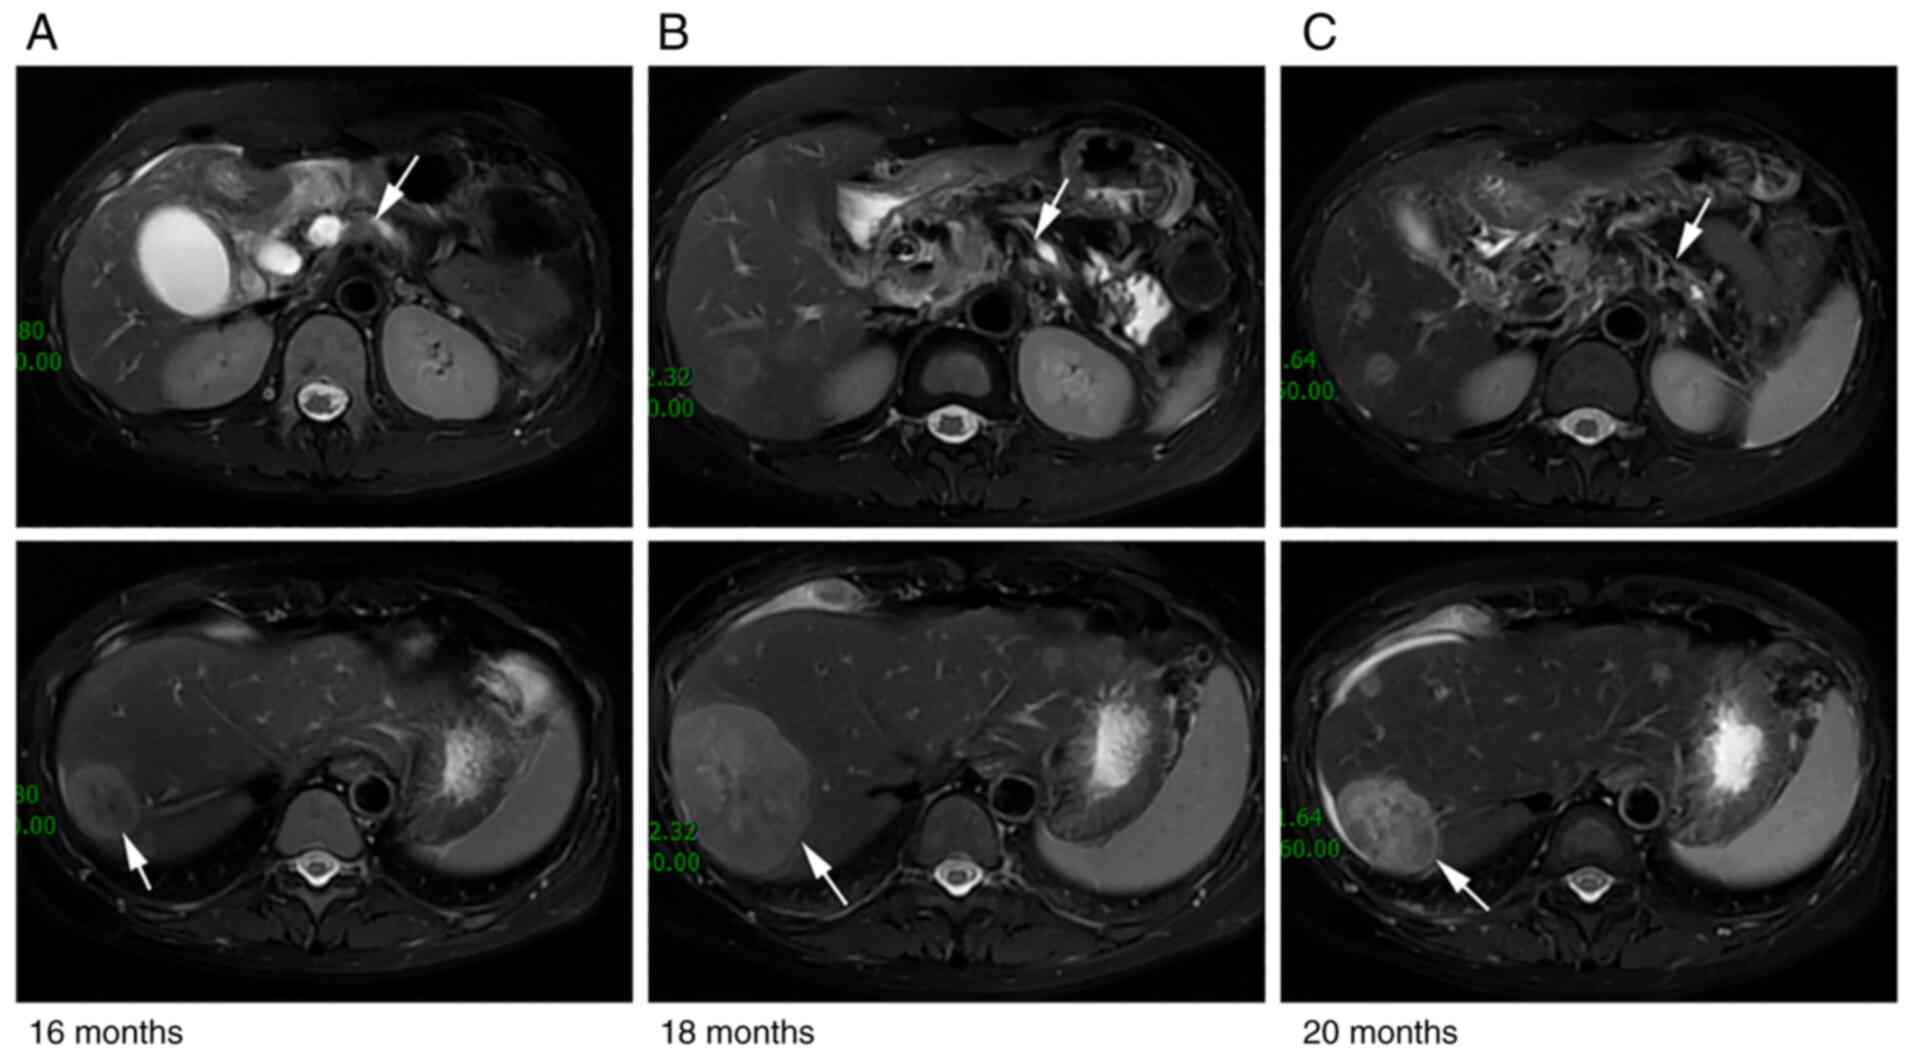

The disease was now considered to be at progressive disease (PD) due to the increasing lesion size in the liver (maximum diameter 2.7 cm) and the target mass in the pancreas (4.3×2.1 cm; Fig. 5A) being similar to that measured previously (4.3×2.0 cm; Fig. 4C) at month 16 after first diagnosis. Since the patient had benefited greatly (evaluated as PR) from the nab-paclitaxel therapy and it had been discontinued for >6 months, the third-line mono-chemotherapy of nab-paclitaxel (125 mg/m2; days 1 and 8; every 3 weeks) was recommended. The patient tolerated this regimen adequately, but the disease progressed and the size of metastases in the liver grew bigger rapidly after two cycles of nab-paclitaxel (Fig. 5B).

Figure 5.

Comparison of abdominal MRI before and after the fourth-line treatment. MRI from (A) before fourth-line treatment at 16 months, and after treatment at (B) 18 and (C) 20 months post-diagnosis. The pancreatic mass appeared to be smaller during the fourth-line treatment, but there was (A) an obstruction in the pancreaticobiliary duct, an accumulation of fluid in the gallbladder, larger liver metastases and larger lymph nodes in the retroperitoneum. (B) The pancreatic mass and liver metastases were enlarged compared with previously (A). (C) The pancreatic mass was large and the liver metastases were small. Arrows indicate the tumors and lesions.

The fourth-line treatment of irinotecan (240 mg; day 1) and anlotinib (8 mg; days 1–14 every 3 weeks) was well tolerated and applied to treat the progressive disease (PD) status (Fig. 5B). The patient accepted tomotherapy palliative radiotherapy (60 Gy over 12 fractions) for the hepatic metastasis. Repeat imaging assessment after four cycles of combination treatment showed a significant reduction in the size of the liver lesions (Fig. 5C). The tumor size continued to decrease and the disease remained stable with no clinical evidence of progression. The tumor marker levels of CA19-9, CA242 and CEA, in addition to those of the inflammatory marker IL-6, decreased again (Fig. 6A-D) and the overall survival (OS) time was extended to 24 months and counting. The general status of the patient is good in July 2022 and the patient will be followed up every 45 days.